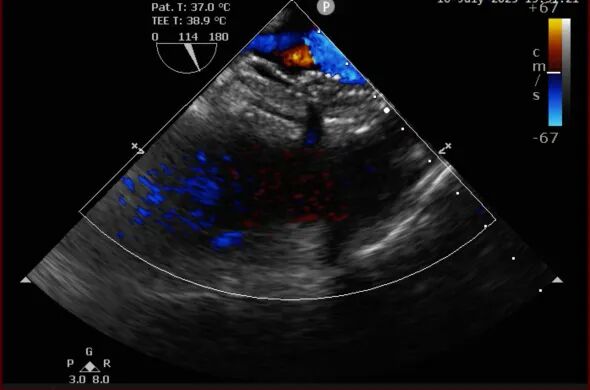

術前和術后TEE圖對比

手術過程中,憑借精湛技術和默契配合,團隊成功將兩枚可降解封堵器精準植入預定位置。術后即時超聲檢查顯示:兩處缺損封堵嚴密,無任何殘余分流,封堵器形態和位置理想,手術圓滿成功。術后,患者恢復良好,順利康復出院。